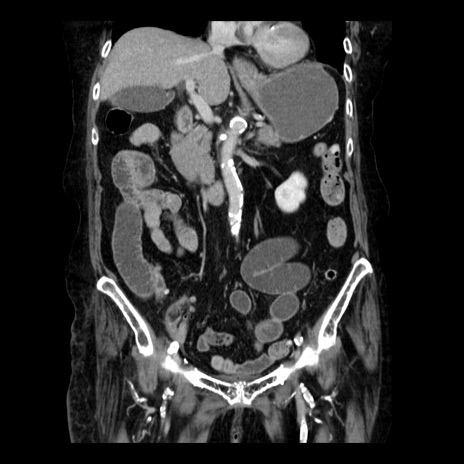

症例14(冠状断像)

【症例】 90歳代女性

【主訴】 腹痛・嘔吐

【現病歴】今朝から左側腹部痛を認めた。 経過観察していたが、嘔吐を認めたため来院。

【既往歴】 子宮癌術後

【身体所見】 意識清明、BP 127/54mmHg、P 98bpm Sp02 95%(RA)、BT 35.8°C、腹部平坦・軟腸ぜん動音聴取良好、右下腹部圧痛(+) 反跳痛なし

【データ】WBC 9800、CRP 0.46